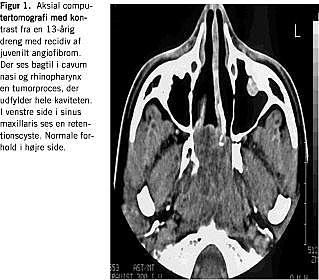

CT skal udføres uden og med kontrast, som koronal og aksial skanning. Denne undersøgelse er især velegnet til at afsløre displacering og udtynding af ossøse strukturer med (Figur 1 ), men MR-skanning er den vigtigste undersøgelse. Ved denne undersøgelse ses, at tumoren udviser kraftig kontrastenhancement efter gadoliniumindgift. MR-skanning skal udføres i tre planer og er især vigtig, når tumorens udgangspunkt og udbredelse skal konstateres (Figur 2 ) [1]. Arteriografi skal udføres som bilateral carotis externa- og interna-arteriografi for at fastlægge tumorens karforsyning. Det er vigtigt, at såvel a. maxillaris interna som a. pharyngea ascendens kan ses, da hovedforsyningen ofte kommer herfra [2].